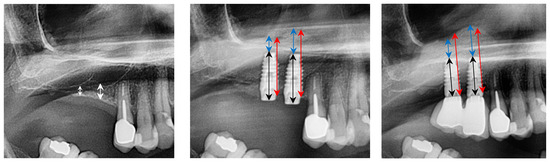

2. Case Presentation